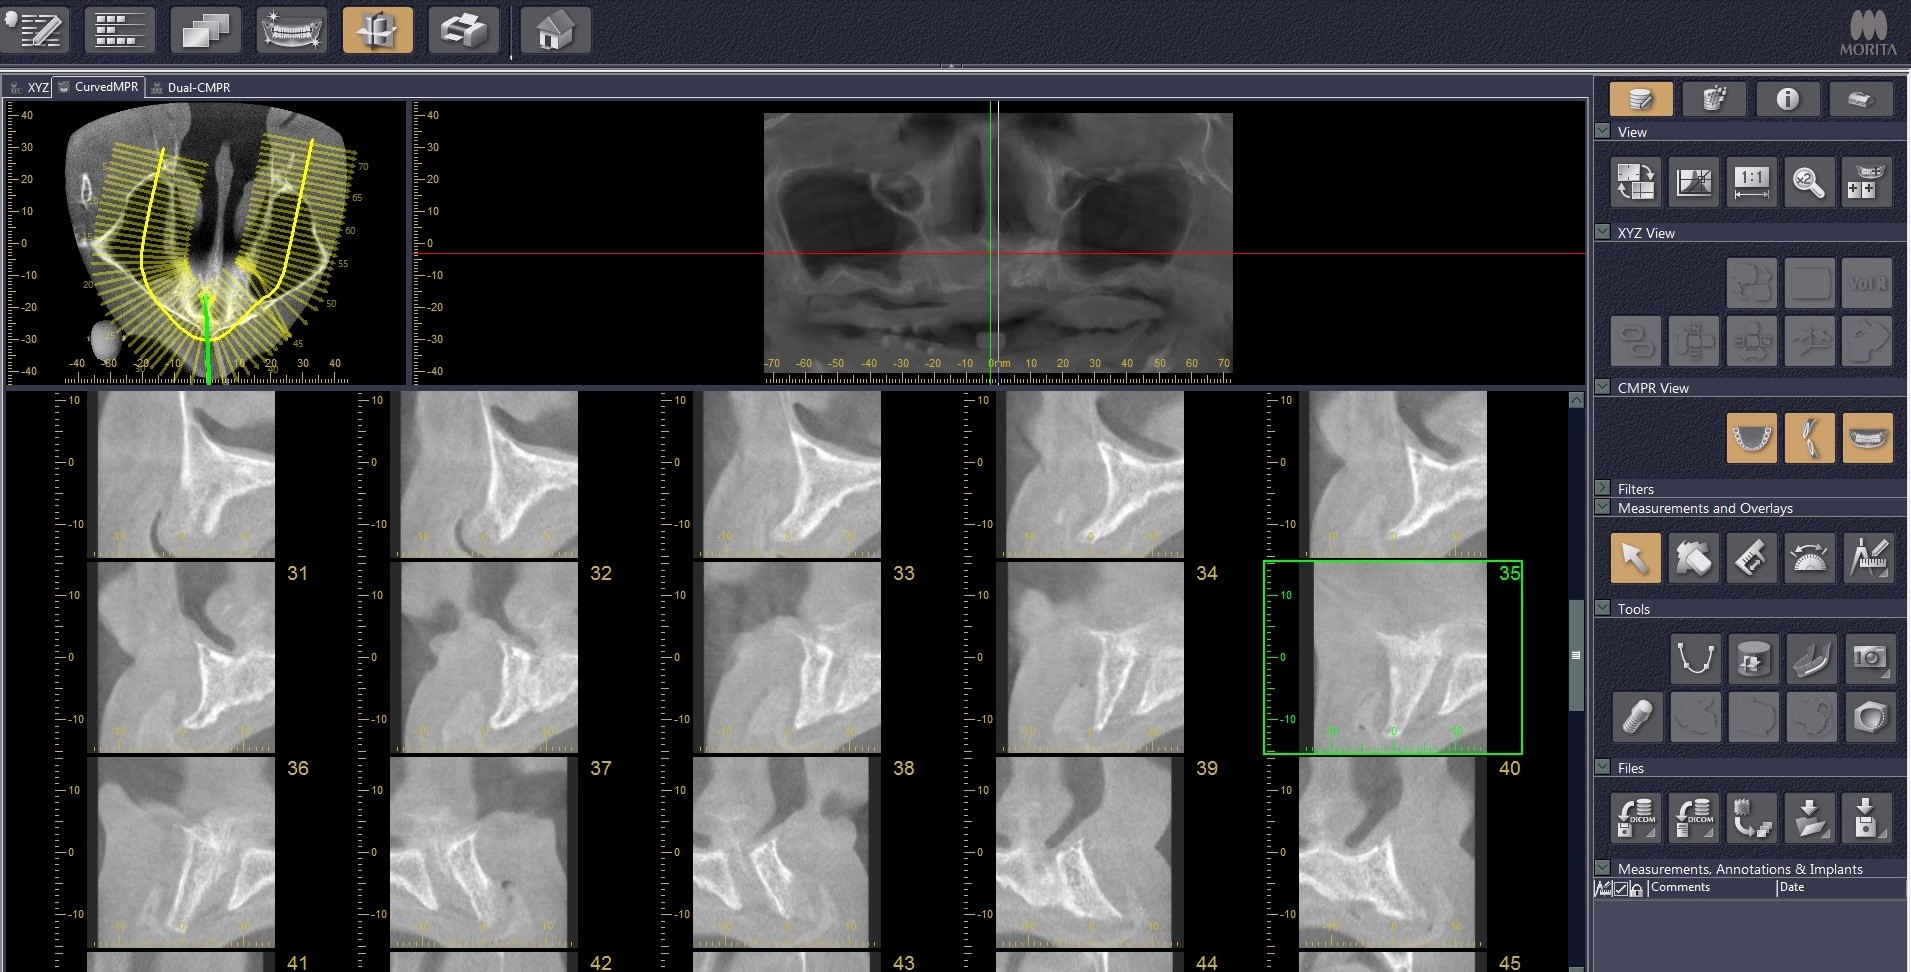

21/21 - Before and after CT scan: approx. 3 mm bone gain

Reconstruction of maxillary ridge with maxgraft® block - Amit Patel